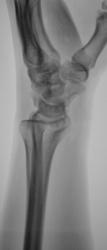

Катенёв Валенти... Дата публикации 13.10.2009, 18:16 Пациент направлен в рентгеновский кабинет хирургом для рентгенографии лучезапястного сустава. Травма. Произведено исследование. pp.1..JPG pp.2..JPG pp.3..JPG pp.4..JPG Ваше мнение коллеги? ВложениеРазмер pp.1..JPG62.4 КБ pp.2..JPG53.6 КБ pp.3..JPG95.92 КБ pp.4..JPG80.54 КБ Втр, 13/10/2009 - 21:14 #1 flagman Не на сайте Был на сайте: 11 лет 5 месяцев назад Зарегистрирован: 05.06.2008 - 20:08 Публикации: 83 странная ладья - неужели перелом? Втр, 13/10/2009 - 21:18 #2 Катенёв Валенти... Не на сайте Был на сайте: 7 лет 3 недели назад Зарегистрирован: 22.03.2008 - 22:15 Публикации: 54876 Один перелом "ладьи"? Втр, 13/10/2009 - 21:29 #3 Павел Владимирович Не на сайте Был на сайте: 16 лет 2 месяцев назад Зарегистрирован: 07.10.2009 - 20:47 Публикации: 11 перелом ладьевидной кости с расхождением отломков Втр, 13/10/2009 - 21:41 #4 Наталия Не на сайте Был на сайте: 8 лет 7 месяцев назад Зарегистрирован: 30.07.2008 - 13:24 Публикации: 538 Двойной перелом ладьевидной кости. Ср, 14/10/2009 - 07:52 #5 v1tal Не на сайте Был на сайте: 4 года 9 месяцев назад Зарегистрирован: 07.06.2008 - 19:41 Публикации: 1779 А как же полулунная ????? Ещё и ладья в предачу. "Знаешь, у некоторых врачей есть комплекс мессии — им необходимо спасать мир. А у тебя комплекс Рубика — тебе необходимо решать головоломки." Ср, 14/10/2009 - 14:38 #6 OPEXOB Не на сайте Был на сайте: 9 лет 11 месяцев назад Зарегистрирован: 26.07.2008 - 10:02 Публикации: 280 Может "снайперы" укажите стрелками, кто, что видет? Ср, 14/10/2009 - 19:48 #7 Глазков Игорь А... Не на сайте Был на сайте: 9 месяцев 2 недели назад Зарегистрирован: 19.12.2008 - 20:41 Публикации: 1597 ладьевидной кости Прийди к Себе

странная ладья - неужели перелом?

Один перелом "ладьи"?

перелом ладьевидной кости с расхождением отломков

Двойной перелом ладьевидной кости.

А как же полулунная ????? Ещё и ладья в предачу.